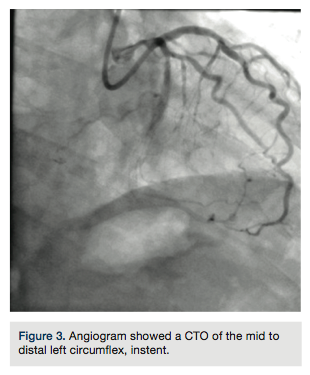

A Pilot 200 wire (Abbott Vascular) was loaded in a CrossBoss catheter (Boston Scientific) and advanced into the circumflex artery. The CrossBoss was slowly advanced, using the Pilot wire to redirect the device to remain as close to the lumen as possible. Once past the total obstruction, the Pilot 200 wire was used to re-enter the distal circumflex (Figures 3-4). A balloon dilation with a 1.5 mm x 20 mm long balloon was performed at 12 atmospheres (atm) followed by a 2.5 mm x 20mm balloon at 12 atm. A Runthrough wire (Terumo) was placed in the first marginal and stenting of the circumflex was performed using a 2.5 mm x 38 mm Promus Premier stent (Boston Scientific) overlapped with a 3.0 mm x 24 mm Promus Premier stent. High-pressure inflation in the entire stented segment was performed using a 3.0 mm balloon. The segment proximal to the first obtuse marginal was dilated to high pressure using a 3.25 mm balloon (Figures 5-7). A good angiographic result was seen (Figure 8).